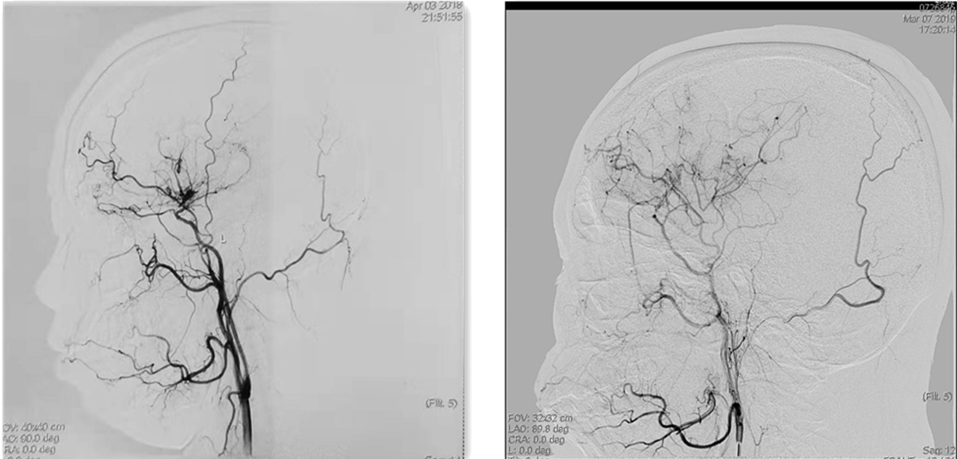

术前左侧颈总动脉造影 术后左侧颈外动脉造影